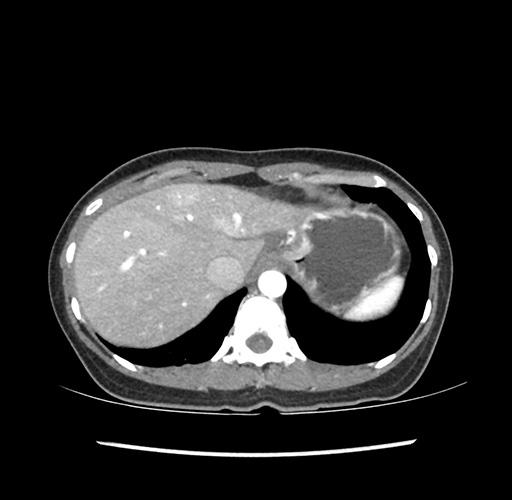

Imaging Analysis

Look through the patient's CT scan to identify any areas of concern for the necessary procedure.

Based on your CT findings, which issue(s) would give reason for "planned slowing down moment(s)" in this case?

Considering a standard left lateral sectionectomy procedure, what step(s) of the operation would you do differently in this case ?